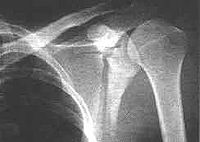

肩胛骨骨折可分为肩胛骨体部骨折、肩胛颈部骨折、肩胛盂骨折、喙突骨折和肩峰骨折。肩胛骨体部骨折是肩胛骨骨折的常见类型,多为粉碎性骨折,肩胛骨体部骨折线可为斜行、纵行或星形,亦可贯通至肩胛岗。由于肩胛骨被肌肉、筋膜紧紧包裹,骨折移位多不明显。